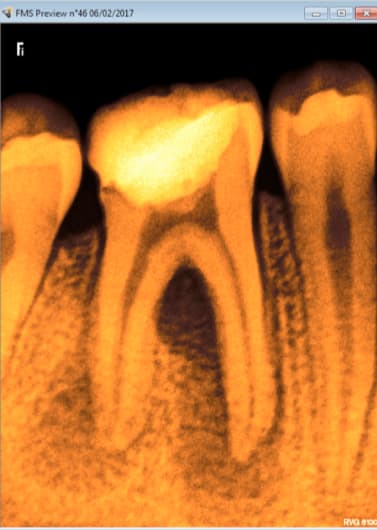

tiens pour revenir au sujet du post:

-> j'ai eu une patiente de 75 ans 16 très calcifiée

-> j'ai dépulpé le palatin

-> les deux autres canaux sont calcifiés à mort et racines courbées

-> que faites vous dans ce genre de cas????

Perso :

- j'ai obturé le P

- j'ai mis de la biodentine dans la chambre

- plus du tout de douleur à 3 semaines

- je vais lui faire un onlay composite

6szjws718sv1jksw54v4mpj3a6cu - Eugenol

Y avait il une indication pour ton endo?